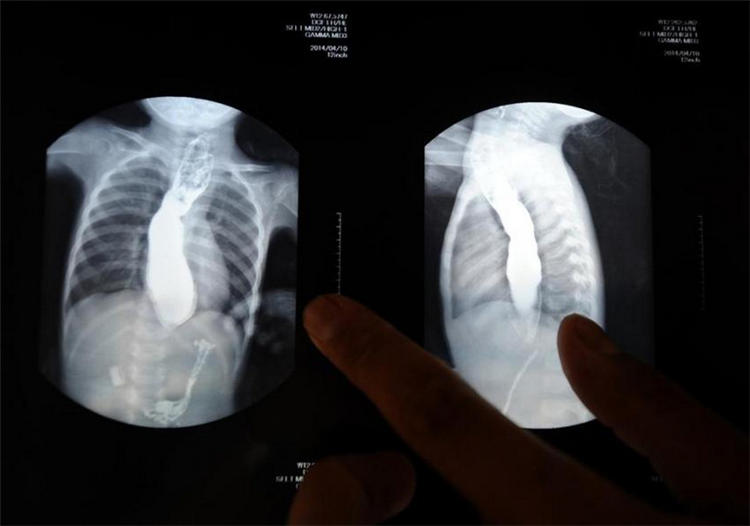

22日、娘が1カ月前に撮影した胸部の寫真を見せる王志華さん。食道が大きく広がっているのに、食べ物は胃に入らない狀態(tài)だ。王可然ちゃんの足は痩せ細(xì)り、體重はわずか7キロしかない。21日、有志の人からプレゼントされたぬいぐるみを抱いてベッドで過(guò)ごす王可然ちゃん。同日、山西省児童病院の病室で、父親の顔を撫でる王可然ちゃん。同日、山西省児童病院の病室で、娘に寄り添って遊ぶ王志華さん。病床の上には有志の人が贈(zèng)ってくれたおもちゃがある。22日、同室の男の子と遊ぶ王可然ちゃん。彼女の背格好はこの自分より1歳半年下の男の子と比べても痩せていて弱弱しい。